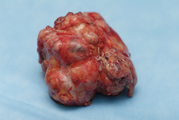

Фиброаденома молочной железы  —  доброкачественная опухоль молочной железы, происходящая из клеток самой железы, возникающая на фоне гормонального нарушения.  Является разновидностью узловой мастопатии.

Чаще всего встречается обычная фиброаденома не перерождающаяся в рак или саркому. Реже встречается быстрорастущая филлоидная (листовидная) фиброаденома, как правило больших размеров, которая может перерождаться в саркому.

Лечение. Показаниями к удалению опухоли являются: быстрый рост опухоли, большие размеры опухоли, подозрение на рак молочной железы, пожелание самой женщины при канцерофобии; 100%-ным показанием к удалению является планируемая беременность.